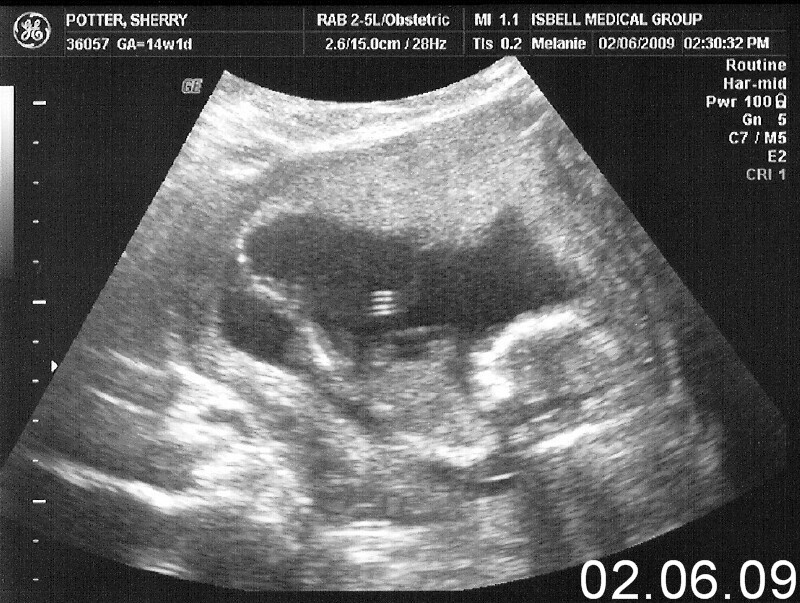

Hayley Grace February 06, 2009

Back to hayley.davidandnell.com